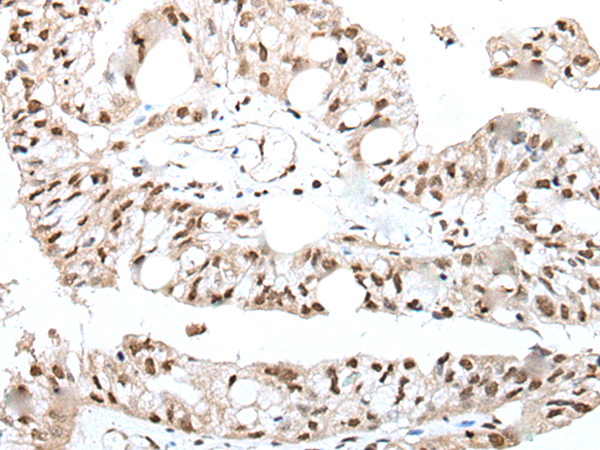

分类: 科研抗体货号: P09329别名: UBP; SIH003应用: IHC反应种属: Human, Mouse